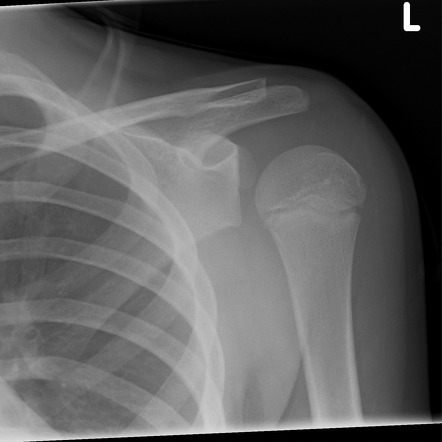

A 32-year-old man is brought to the emergency department after a seizure. He complains of pain and limited movement in his left shoulder. On examination, the shoulder appears held in internal rotation with limited external rotation and anterior fullness is absent. There is tenderness over the posterior shoulder region. An X-ray of the left shoulder (see image) is performed.

Which of the following is the most likely diagnosis?

A) Right anterior shoulder dislocation

B) Right posterior shoulder dislocation

C) Right clavicle fracture

D) Right proximal humerus fracture

E) Rotator cuff tear